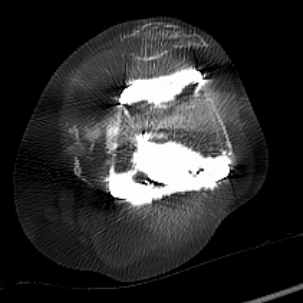

▲CT提示:假体松动,

内侧股骨髁、内侧胫骨平台骨缺损严重